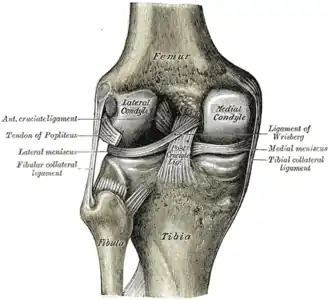

Na anatomia, os meniscos são cartilagens presentes na articulação tíbiofemoral (região do joelho), entre os côndilos do fêmur e da tíbia. Os meniscos têm a função de diminuir o impacto e promover a adaptação (melhorar o encaixe) entre as faces articulares do fêmur e da tíbia.[1] Melhoram a congruência das superfícies articulares[2], além de dar mais mobilidade, lubrificação ao joelho.[3]

São dois meniscos, um medial e outro lateral, ambos localizados acima da tíbia. Têm o formato de meia lua, com uma divisão em corno anterior, corpo e corno posterior. Como cartilagem, apresentam poucos vasos sangüíneos, o que dificulta sua capacidade de regeneração, caso sofram alguma lesão. Uma vez lesionados, dificilmente se recuperam espontaneamente.

Os cornos dos meniscos possuem distancias, sendo que os do externo estão mais próximos entre si que os internos. E não estão livres no espaço articulares, mantendo uma junção funcional.[4]